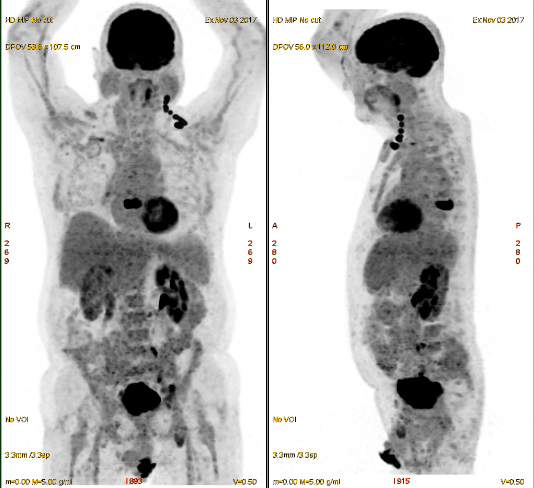

Vous recevez les résultats du TEP-TDM au 18-FDG.

Question n°7 : Vous identifiez comme localisations tumorales

Fixation myocardique physiologique (activité myocardique)

Fixation rénale physiologique : filtration rénale du traceur, idem dans la vessie

Fixation encéphalique physiologique (activité encéphalique). La méningite carcinomateuse est un diagnostic fait à l’imagerie par résonance magnétique (IRM) et sur la ponction lombaire

On rappelle que l’examen neurologique est sans particularité.